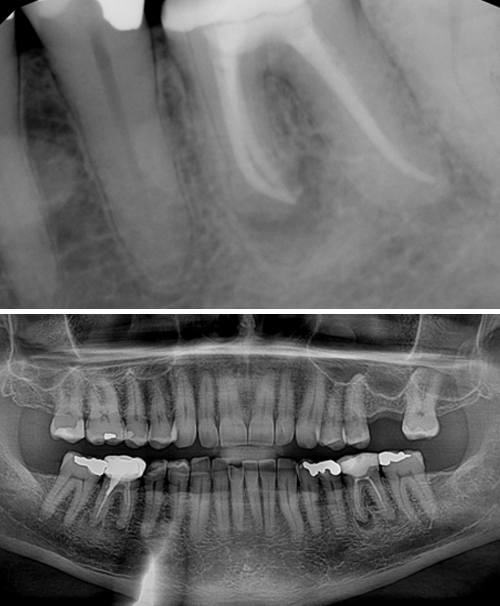

Csontpótlás

Alsó és felső állcsontba nem mindig lehet foghúzás után implantálni. Sokszor hiányzik a megfelelő csont szélesség és magasság. Ebben az esetben először a csontot kell pótolni, és utána implantálni.